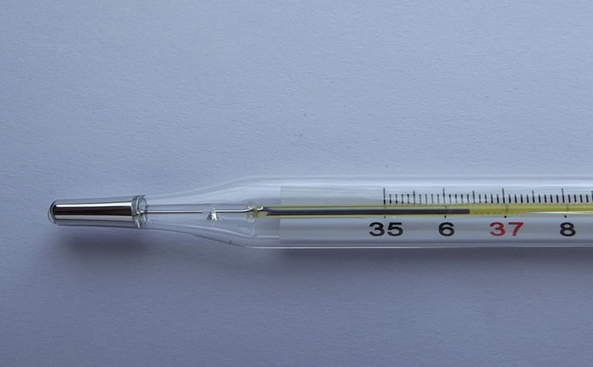

160年历史终结!我国将于2026年禁产水银体温计 告别甩一甩时代

水银体温计禁产不等于禁售:有网店一天卖超300支